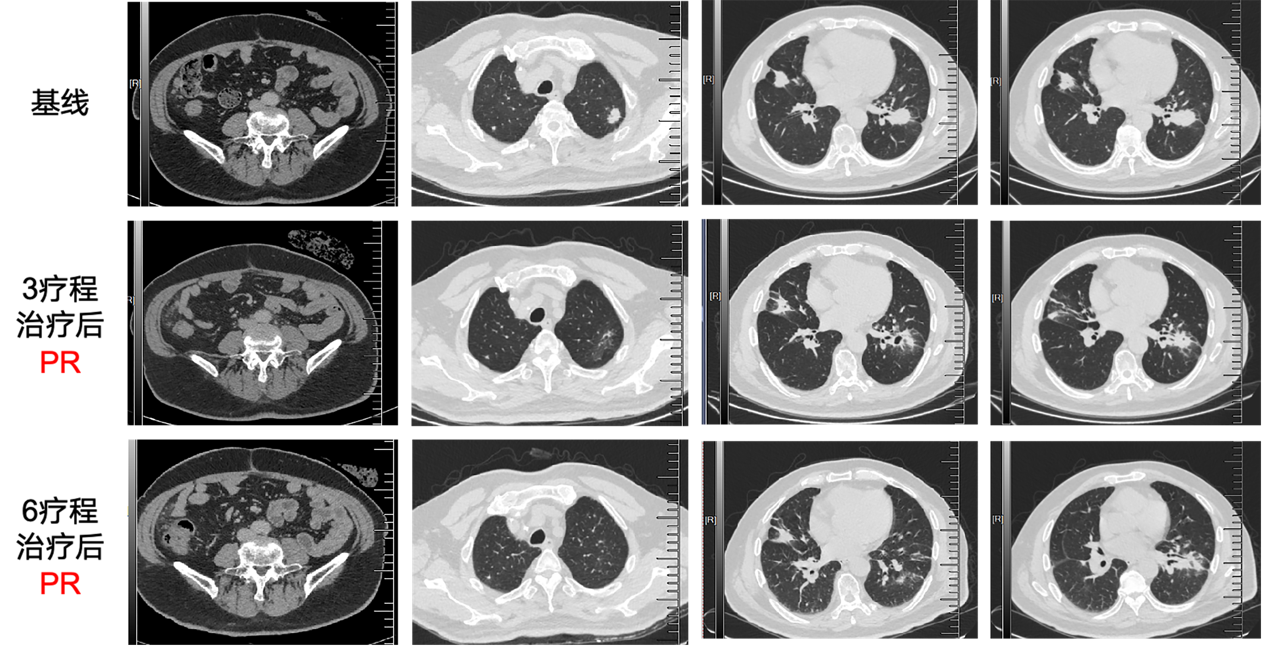

接受11个周期 FOLFOX联合西妥昔单抗方案, 疗效评估PR,治疗期间出现 1级低镁血症不良反应,对症治疗后好转。

2024.11

复查CT提示肺部病灶增大, 考虑PD,PFS1为6.5个月。

图1 影像学评估.png

图1 影像学评估

2024.03

复查CT提示肺部病灶及肝内转移灶,较前均明显缩小,疗效评估PR。

2025.06

复查CT提示肺部病灶及肝内转移灶,较前均明显缩小,疗效评估PR,患者持续规律CAP方案治疗,定期随访。

图片5.png

图5 影像学评估